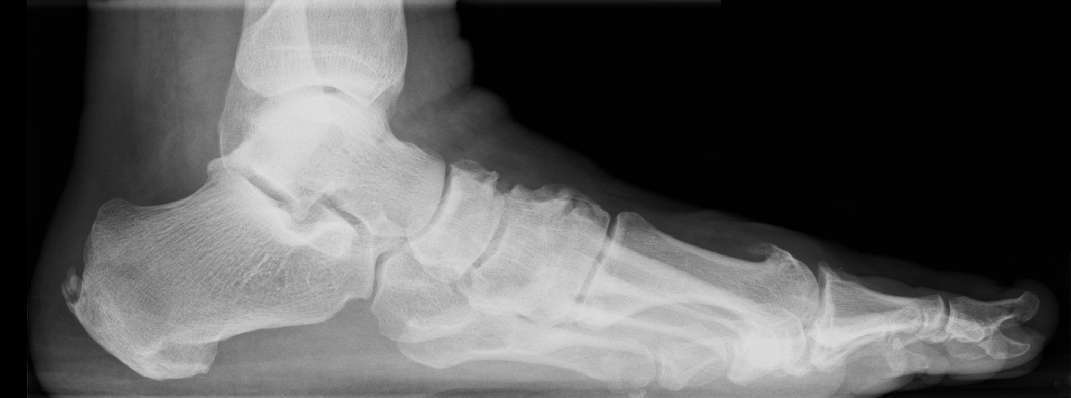

Degenerative change can affect a number of joints in the midfoot

The midfoot contains several small joints that connect the forefoot to the hindfoot. These joints help the foot adapt to uneven ground, absorb shock, and create a stable platform for movement.